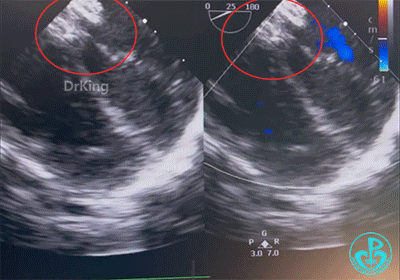

先后展开左右盘面并前推钢缆辅助成型,而后确认封堵器位置是否合适并评估血流。

经评估,封堵器形态大小合适,彩超提示无血液分流。